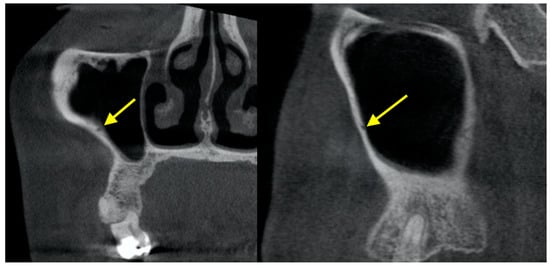

3. Pathology